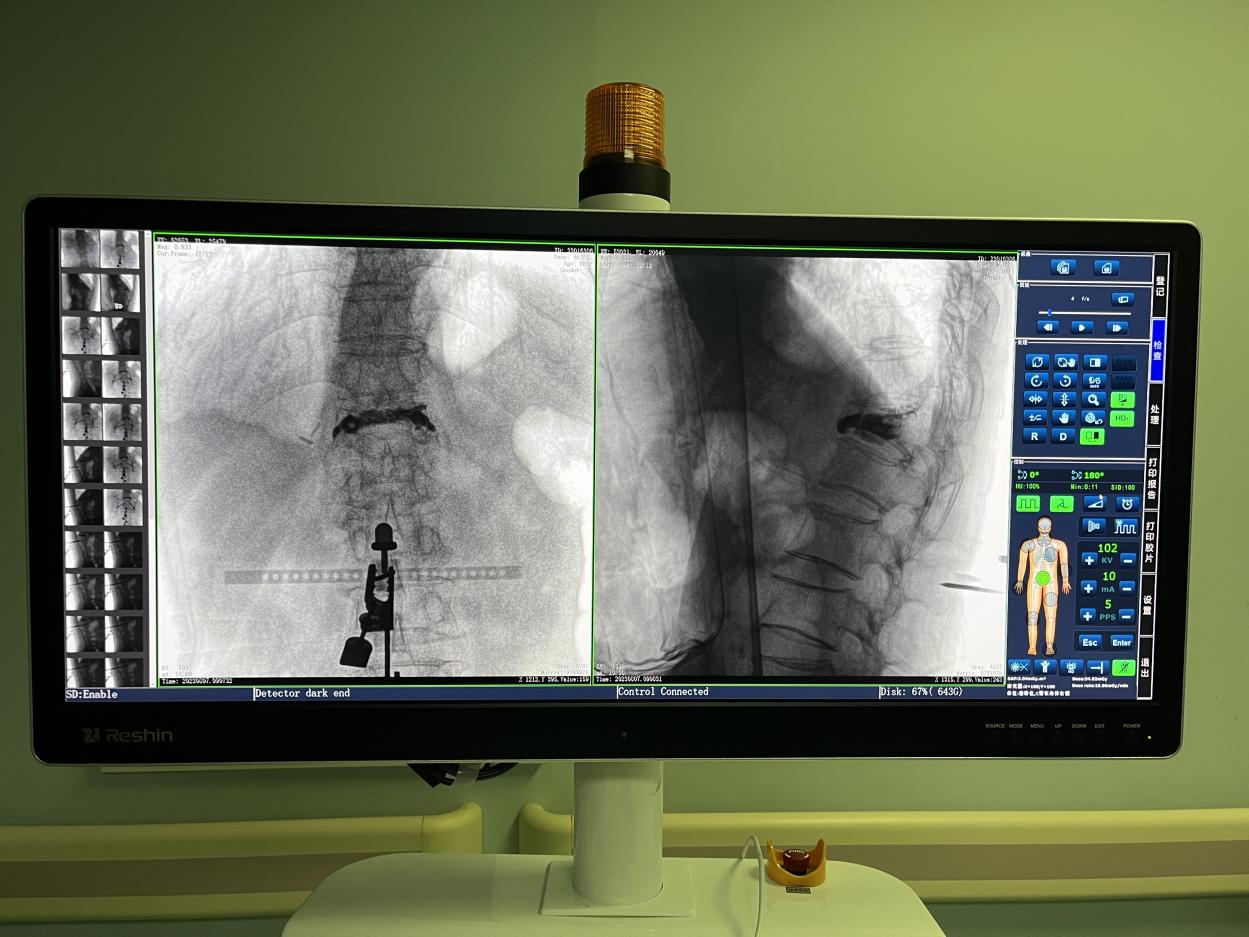

4.微創(chuàng)皮膚切口

傳統(tǒng)的開放式手術(shù)需暴露手術(shù)可見視野,以便醫(yī)生獲得更多的判斷信息,手術(shù)創(chuàng)口大,術(shù)后恢復(fù)時間長。而在骨科機(jī)器人輔助的微創(chuàng)手術(shù)中,手術(shù)創(chuàng)口僅為1~2厘米左右的小切口,創(chuàng)傷小、恢復(fù)快。

骨科機(jī)器人手術(shù)-術(shù)后影像